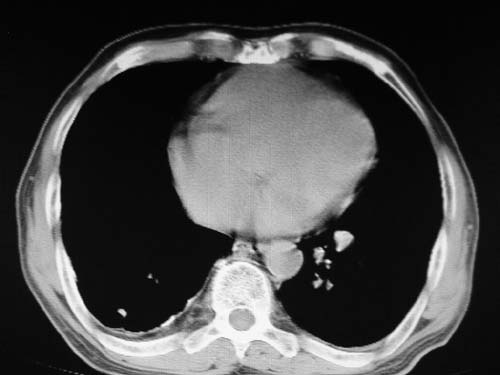

男,80岁

双肺陈旧性病变,左肺动脉高压.

结合患者年龄,不除外左下肺扩张性动脉瘤,建议胸透是否有扩张性博动,以便确诊。

肺动脉高压,左肺动脉瘤样扩张。

肺a高压